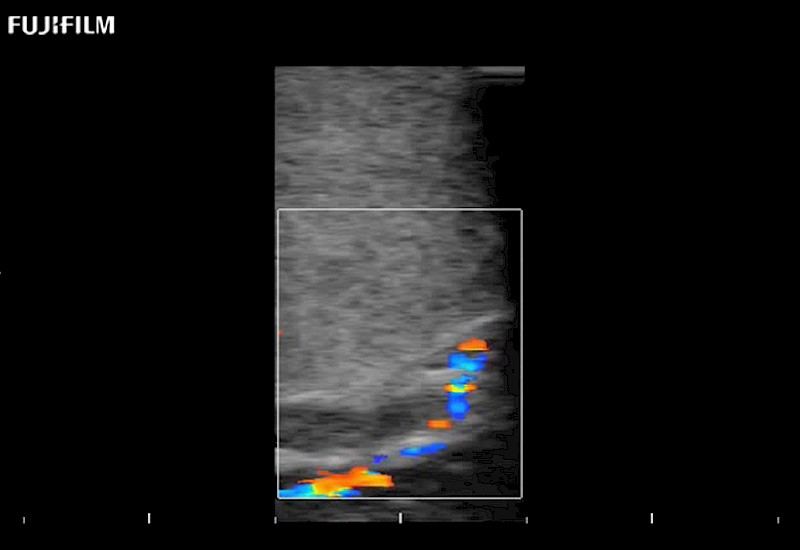

Exclusive 10mm side‐fire linear array transducer with 2.87mm diameter is ideal for real‐time visualization through and behind structures and instant, scalable definition of anatomy and vascularity including the ability to delineate and define tumor margins.